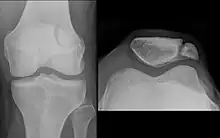

In this X-ray, an anatomical variation of the patella can be seen – the bipartate patella, in which the patella is split into two parts.

Emarginations (i.e. patella emarginata, a "missing piece") are common laterally on the proximal edge.[1] Bipartite patellas are the result of an ossification of a second cartilaginous layer at the location of an emargination. Previously, bipartite patellas were explained as the failure of several ossification centres to fuse, but this idea has been rejected. Partite patellas occur almost exclusively in men. Tripartite and even multipartite patellas occur.